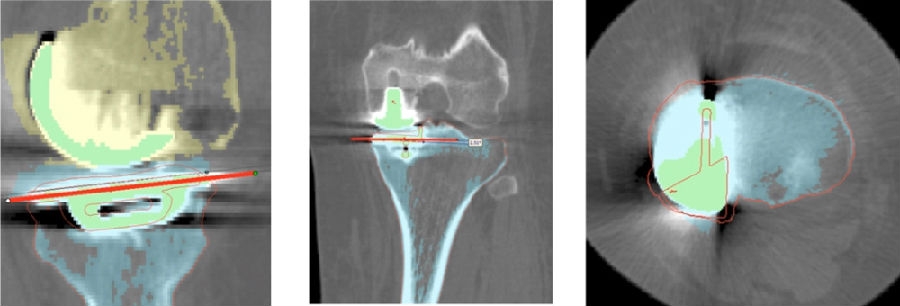

3D打印截骨导板术前规划,要跟工程师细致认真的沟通,三维假体的位置,以及导板相应的贴附区。

术前确认方案,包括大小型号,冠状矢状以及轴面上不同位置,如何选择每个人比较合适的假体相关位置。

术前确认方案

同时,笔者团队也在和导板公司进行合作,把用术后CT和术前CT进行匹配,来验证术前规划的偏离度有多少,包括胫骨后倾、冠状面内倾、轴面胫骨假体旋转、股骨在冠状面的角度、股骨在轴面上的旋转角度以及在矢状面上屈伸角度。

符合度验证